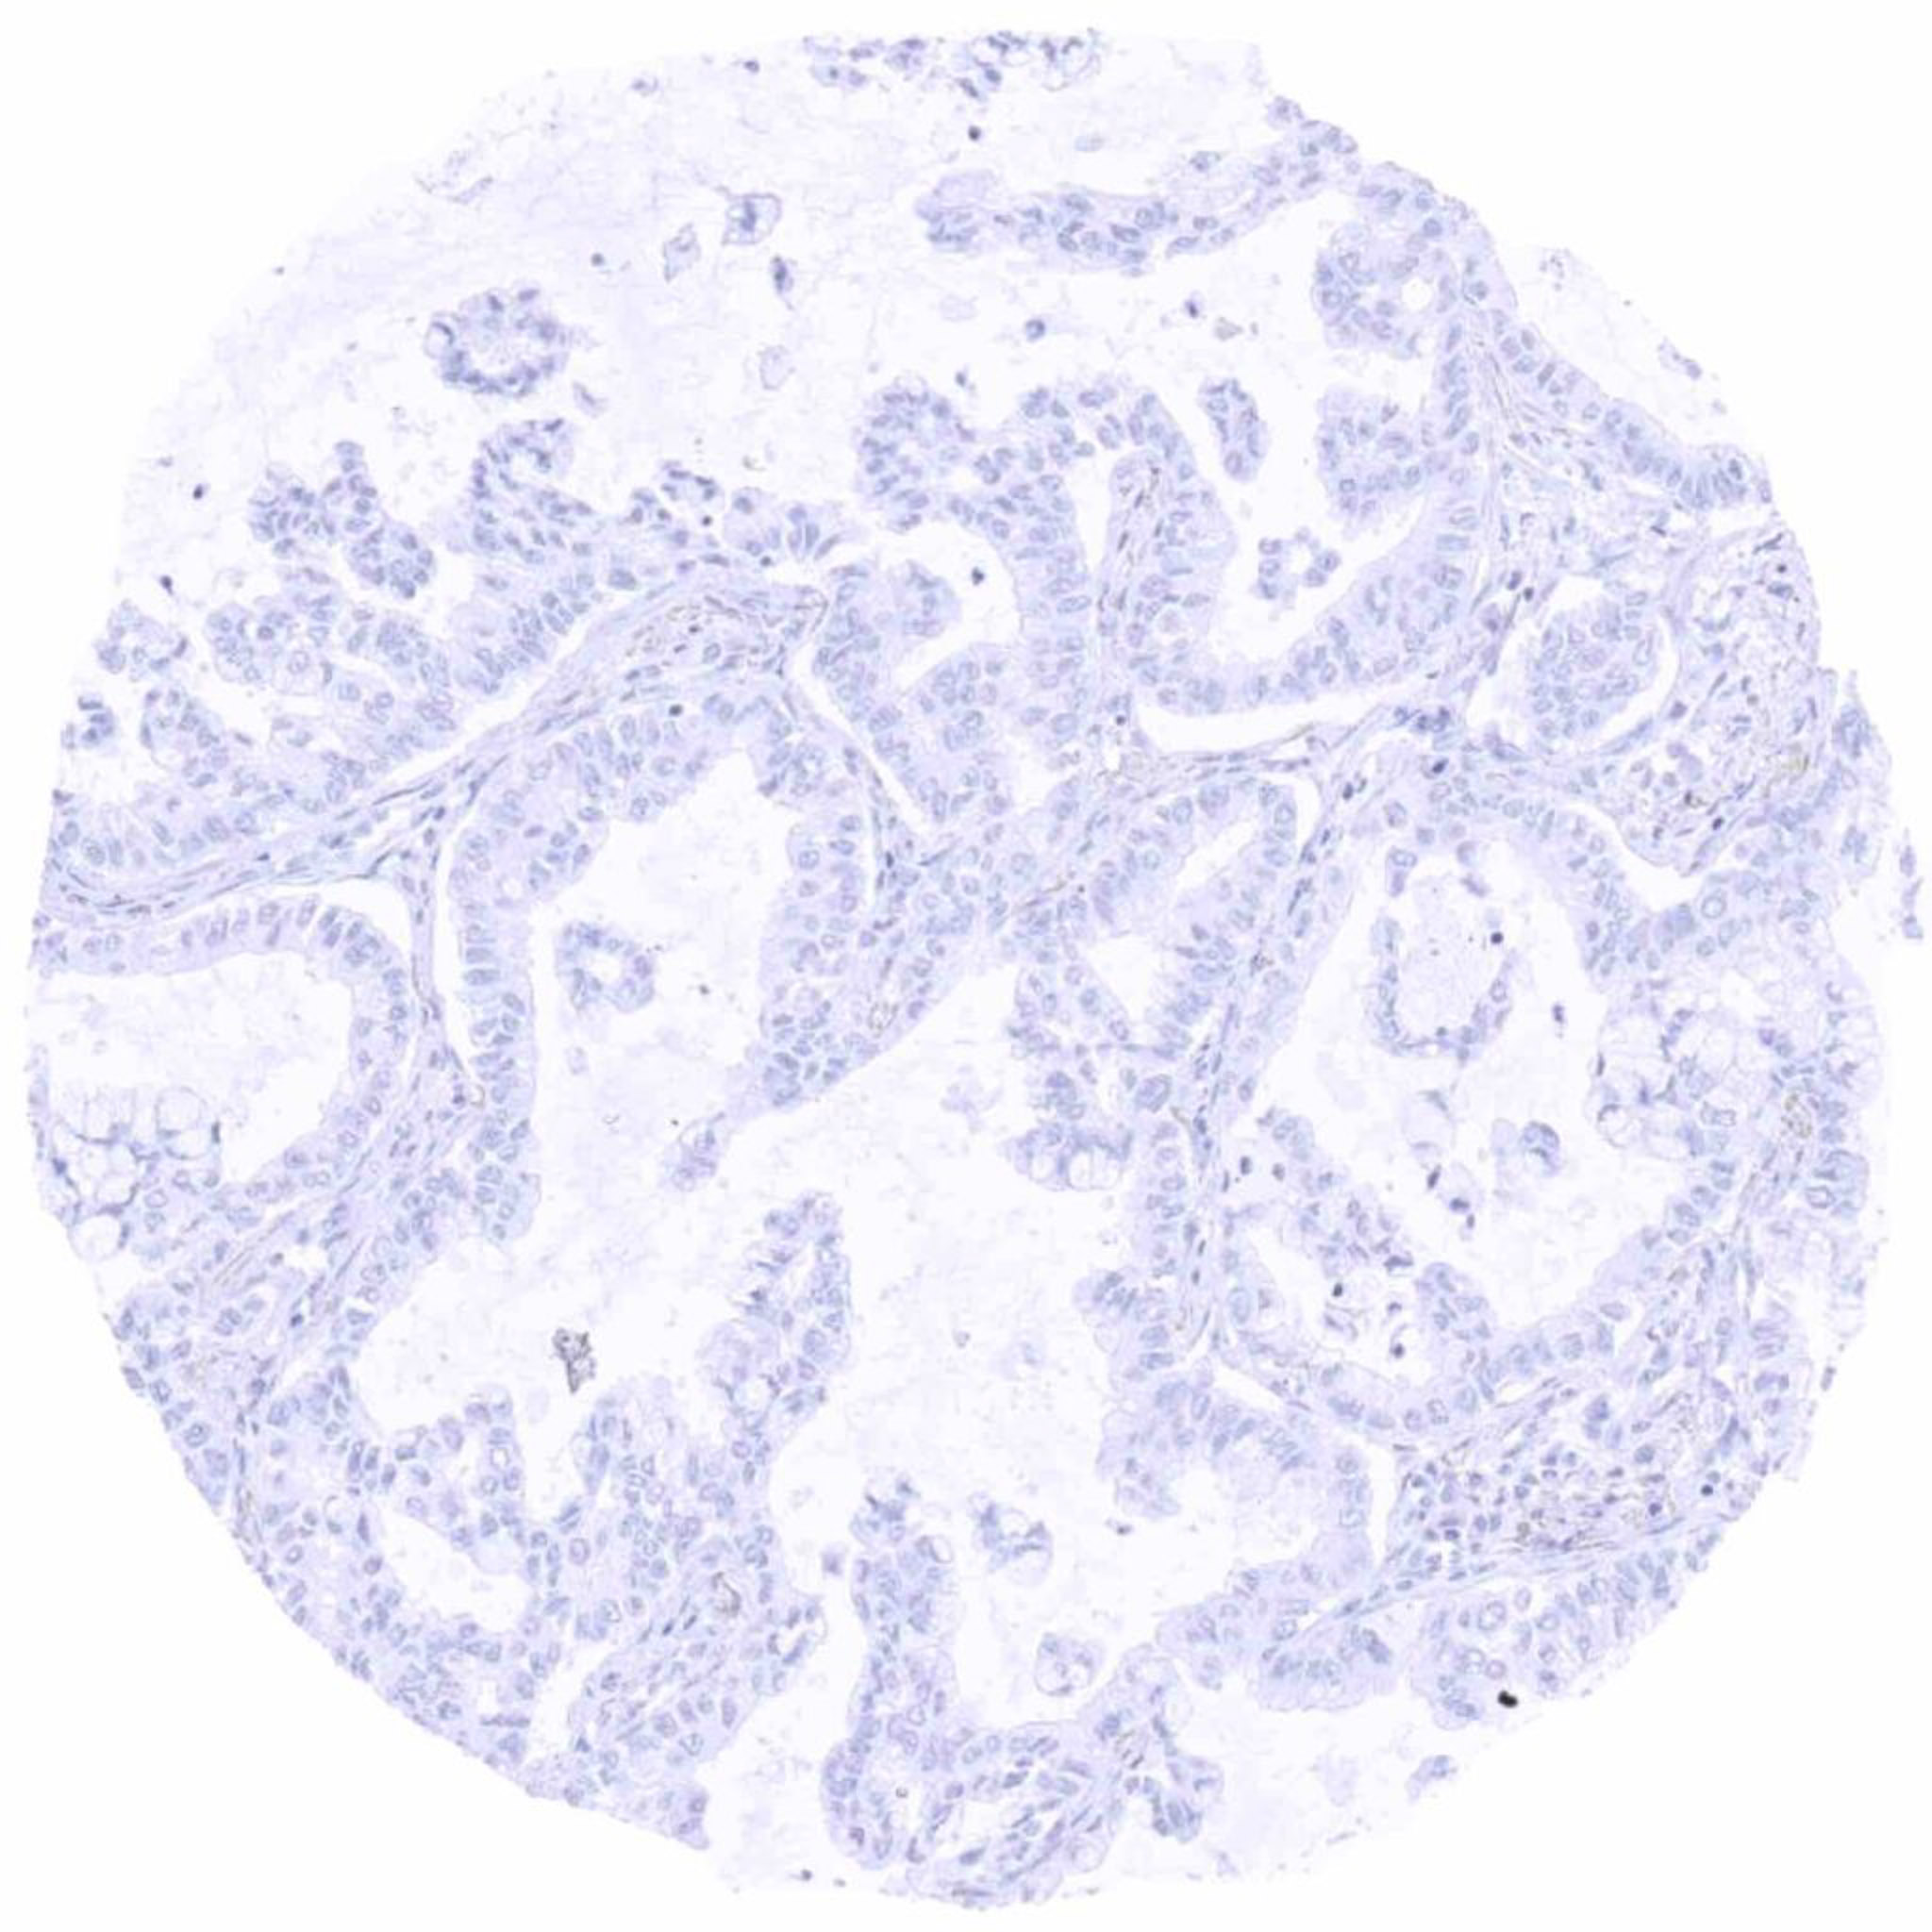

Lung – UPK3B negative adenocarcinoma (1)

Lung – UPK3B negative adenocarcinoma (2)

Lung – UPK3B negative adenocarcinoma (3)